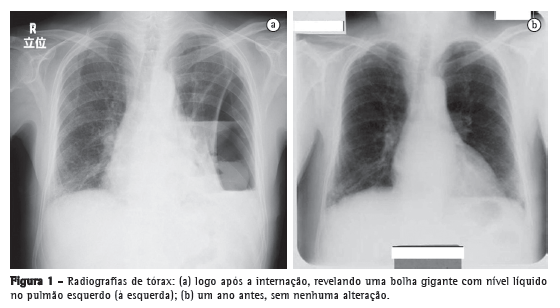

Um homem de 79 anos de idade buscou tratamento no pronto-socorro devido a um histórico de 3 meses de febre persistente, dor torácica e fadiga geral. Apresentava carga tabágica de 60 anos-maço e fizera uso pesado de saquê japonês (180 mL/dia) durante os últimos trinta anos. Os exames laboratoriais realizados indicaram a presença de inflamação grave, e a radiografia de tórax revelou uma bolha gigante de 24 cm de diâmetro no pulmão esquerdo (Figura 1a). Segundo o próprio paciente, não apresentava histórico de alterações radiográficas, e seu último check-up médico, realizado no ano anterior, não revelara anormalidades (Figura 1b). A TC de tórax revelou que a bolha continha líquido e media 4.5 × 17 × 24 cm (Figura 2). O paciente foi diagnosticado com abscesso pulmonar e foi internado em nosso hospital.

Embora tenham sido propostas diversas teorias a respeito da etiologia de bolhas gigantes, a origem dessas bolhas ainda é controversa. Sugeriu-se que bolhas gigantes ocorrem devido ao suposto "mecanismo valvular",(3) à oclusão brônquica ou à transformação das artérias pulmonares e brônquicas.(7) Na verdade, o único outro mamífero no qual o enfisema pulmonar ocorre espontaneamente é o cavalo, e um estudo experimental em cavalos mostrou que a oclusão da artéria brônquica desempenha um papel importante.(2) A maioria dos investigadores concorda que lesões degenerativas fazem com que as paredes alveolares percam sua elasticidade.(2) À medida que as paredes se expandem, os alvéolos ficam maiores e alguns se rompem, permitindo o escape de ar para dentro do parênquima pulmonar, resultando na formação de blebs e bolhas.(2) Fain et al. atribuíram a formação de bolhas gigantes ao fumo, que diminui o fluxo sanguíneo para os alvéolos.(2) No caso apresentado aqui, a bolha gigante pareceu ter crescido rapidamente, visto que nenhuma alteração havia sido encontrada durante o check-up médico conduzido no ano anterior. Presumimos que o mecanismo valvular relacionado ao tumor no brônquio inferior esquerdo tenha promovido o crescimento da bolha.